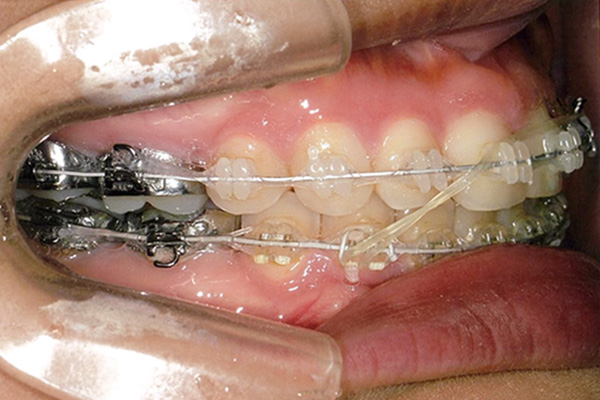

20代 女性

| 症状 | 下顎第一大臼歯の欠損 |

| 想定されるデメリット | 臼歯の近心移動が非常に難しい。高度なテクニックが必要である。 3D-LST矯正治療法を用い、抜歯を最小限に抑えながら歯の近心移動を実施。 |

治療経過

24ヶ月後